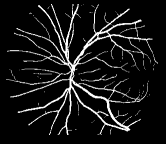

Figure 3: Network architectures of HED, DSN, BS-DSN and BTS-DSN. (a) HED with five side-output layers; (b) DSN with four side-output layers; (c) BS-DSN (DSN with bottom-top short connections); (d) BTS-DSN (BS-DSN with top-bottom short connection)

As is well known, it is hard to optimize a deep neural network due to the gradient vanish problem [28]. To alleviate the gradient vanish problem and obtain a good vessel map, we use deep supervision information in the BTS-DSN. Figure 3 gives an illustration of HED, DSN, BS-DSN and BTS-DSN. We can observe that DSN is based on HED except that there are only four side-output layers, and extra hidden layers are added in DSN for better utilizing deep supervision information. When bottom-top short connections are added to DSN, we get BS-DSN. Further, when top-bottom short connection is added to BS-DSN, we get BTS-DSN.